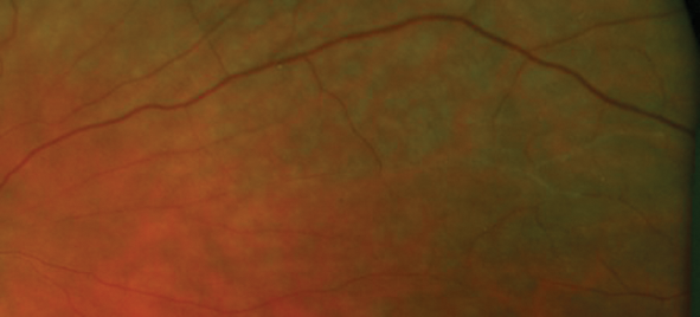

Figure 4: Closer examination of peripheral retina.

What is noticeable in Figures 1a and 1b? And what is the clinical sign shown in Figure 4?

1. Figures 1a and 1b show signs of retinal occlusive microangiopathy with areas of branch retinal artery and arteriolar occlusion. Note the accompanying areas of retinal ischaemic oedema. Figure 4 shows silver-wiring signs on a major arteriole. This is a late common vascular feature after complete vascular shutdown.